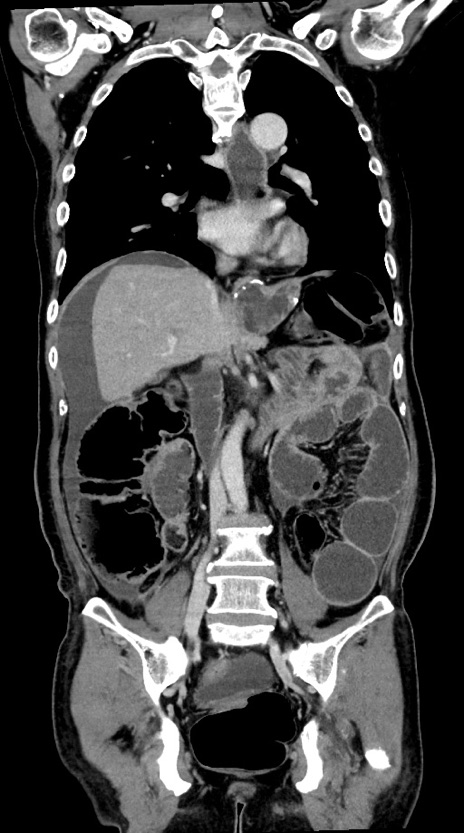

症例28(冠状断像)

【症例】60歳代男性

【主訴】嘔吐

【現病歴】胃癌にて胃全摘後。食思不振が悪化し、夜中に嘔吐することがある。

【既往歴】胃癌、胃全摘、脾摘、胆摘後

【データ】WBC 5900、CRP 10.56